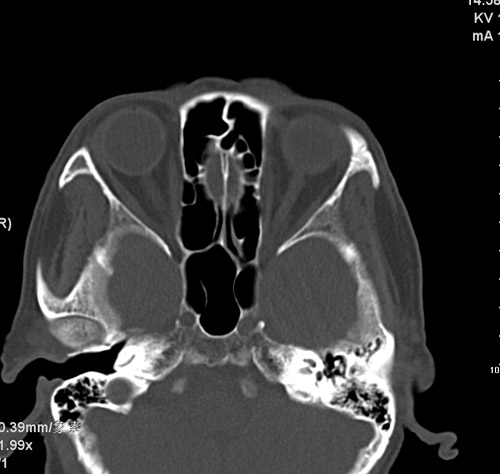

标题: CT17755:女,74 左鼻旁肿胀半年,临床以左上颌窦旁占位行CT [打印本页]

标题: CT17755:女,74 左鼻旁肿胀半年,临床以左上颌窦旁占位行CT

ct考虑鼻前庭囊肿 或鼻翼基底部慢性炎症,左上颌窦少许炎症 请指教

1)考虑左侧鼻前庭囊肿并感染。2)双侧上颌窦炎。

左侧鼻前庭囊肿并感染。双侧上颌窦炎。支持